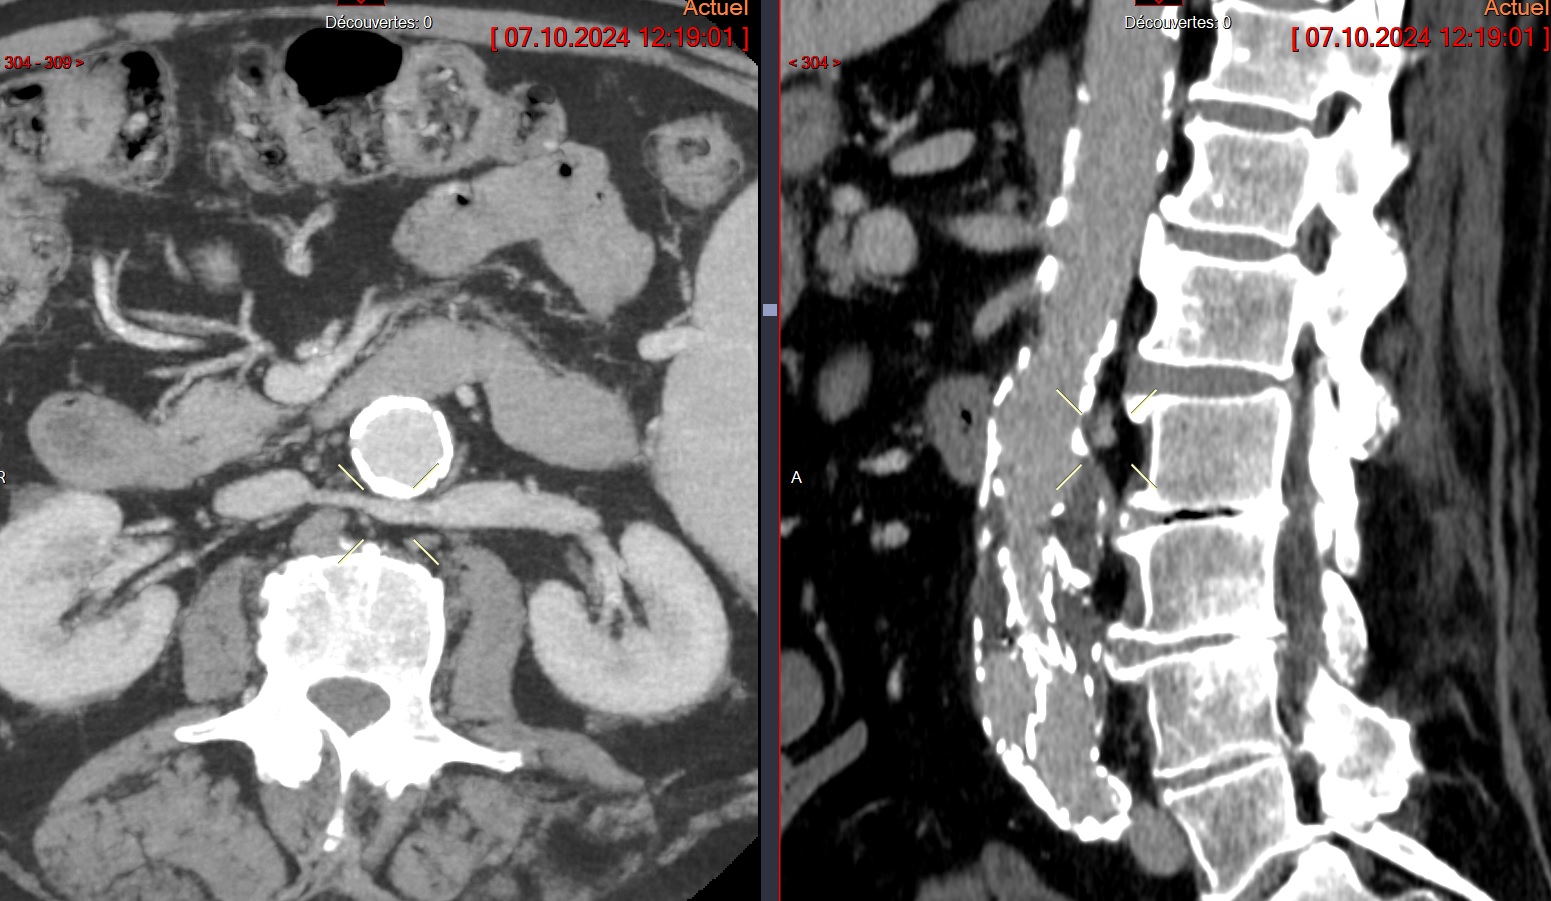

Cas

Veine renale circumaortique

Veine renale circumaortique